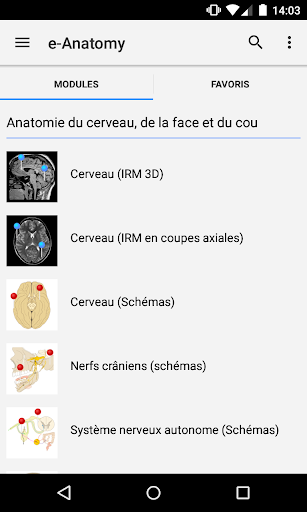

جديد: يمكنك الآن تصفية الوحدات حسب المنطقة أو نوع المحتوى حتى تتمكن من العثور على الوحدة التي تبحث عنها بشكل أسرع.

- وحدتان جديدتان: الدماغ - TOF والأوعية الدموية الدماغية ، أطلس التشريح الوعائي العصبي الطبيعي لشرايين الدماغ على الأوعية الدموية الدماغية. - تم إعادة صياغة الواجهة. - تتوفر علامة تبويب جديدة باسم "QuickLinks" ، ترسل وحدات في أقسام من جسم الإنسان وتسمح لك بالسفر السريع إلى الوحدات التي تبحث عنها. الخلل الصغيرة الثابتة.